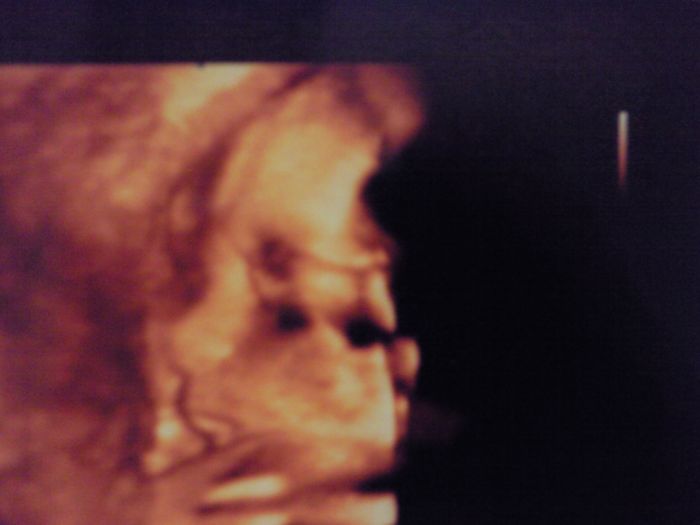

Tak my měli dneska velký utz, prcík má 1500g a je hlavičkou nahoru, ale zatím to je prý jedno, tak doufám, že příště už bude hlavičkou dolů

.. Jinak se nechtěl fotit, čumáček zabořil do placenty, ale pak se nám podařil aspoň krapet profil, je to celý tatínek

Bellinko, krásná fotečka - Víteček tam má takový zadumaný výraz

Bell je tam krásně vidět nosíček i pusinka